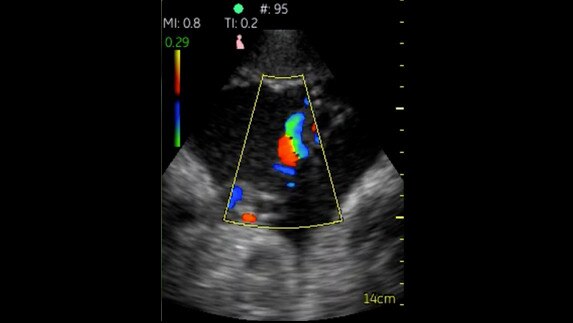

Phased Cardiac